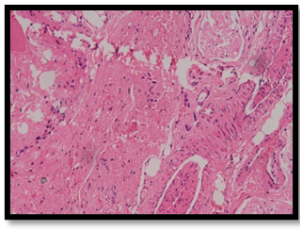

A comparative study of biological reactions to different suture materials in animal model

Sutures play an important role in wound healing. The search for more appropriate suture material has resulted in a variety of natural and synthetic, absorbable and non-absorbable sutures available commercially. These features influence biological reactions to the sutures.

J Exp Mol Pathol, 2025, Volume Volume 2, Issue Issue 1, p15-27 | DOI: 10.46439/pathology.2.008